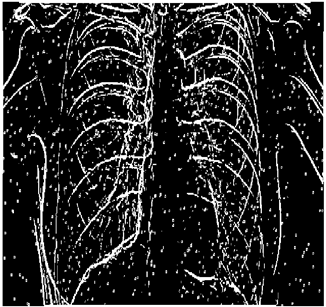

Table 5. X-ray Images.

X-ray 1X-ray 2X-ray 3X-ray 4X-ray 5

Mathematics 10 02421 i004 Mathematics 10 02421 i005 Mathematics 10 02421 i006 Mathematics 10 02421 i007 Mathematics 10 02421 i008

For the purpose of simulation, we consider two sets of images: (1) three images from MATLAB repository (Table 4) and (2) five X-ray images available online (Table 5).

Table 10 shows the following:

• In all cases, the Canny edge detector detects more edge pixels than both fuzzy compositions.

• As the level of noise increases, Canny and standard composition become adversely affected by the noise, and still more edges are detected by Canny; however, most of the detected edges by Canny are misdetections due to the impact of noise. As is obvious from this table, the smooth composition provides a better image with reduced noise density.

• In all cases, the PFOM value for the smooth composition is always greater than the PFOM value for the standard composition, according to Table 6.